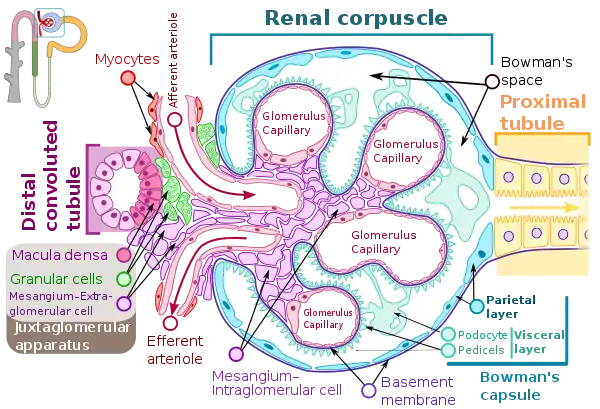

The glomerular basement membrane of the kidney is the basal lamina layer of the glomerulus. The glomerular endothelial cells, the glomerular basement membrane, and the filtration slits between the podocytes perform the filtration function of the glomerulus, separating the blood in the capillaries from the filtrate that forms in Bowman's capsule.[1] The glomerular basement membrane is a fusion of the endothelial cell and podocyte basal laminas,[2] and is the main site of restriction of water flow.[3] Glomerular basement membrane is secreted and maintained by podocyte cells.

The glomerular membrane consists of mesangial cells, modified pericytes that in other parts of the body separate capillaries from each other. The podocytes adjoining them have filtration slits of diameter 25 nm that are formed by the pseudopodia arising from them. The filtration slits are covered by a diaphragm that includes the transmembrane protein nephrin.

Renal corpuscle (glomerulus) showing glomular basement membrane.

Renal corpuscle (glomerulus) showing glomular basement membrane.